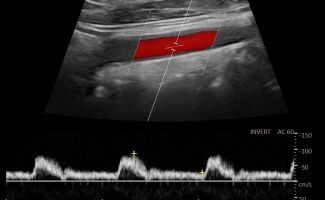

- Έγχρωμο Doppler: Αξιολογεί την ταχύτητα και την κατεύθυνση της ροής του αίματος, προσδιορίζοντας την ύπαρξη και το ποσοστό στένωσης των αρτηριών.

- Παλμικό Doppler: Παρέχει πληροφορίες για τις διακυμάνσεις της ροής του αίματος, βοηθώντας στην αναγνώριση πιθανών αιμοδυναμικών διαταραχών.